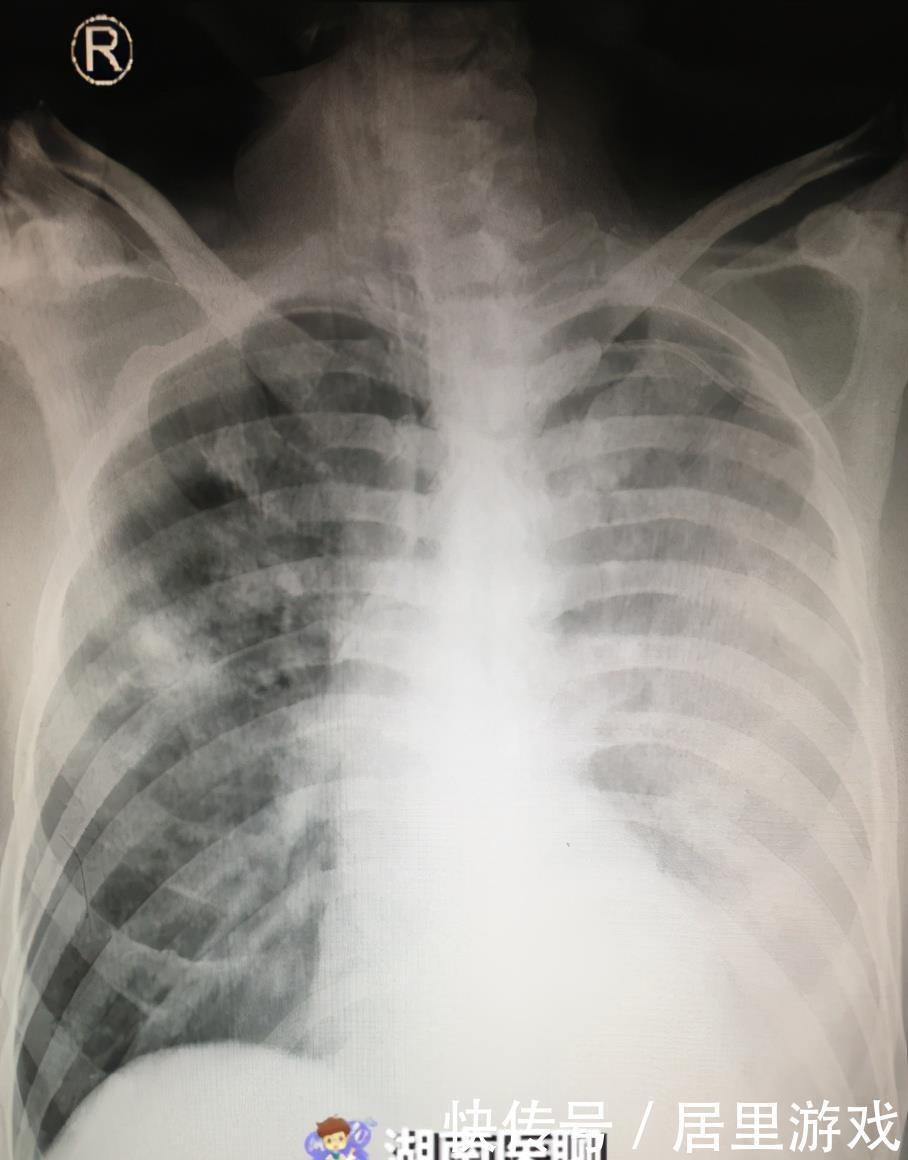

文章插图

(患者入院胸片)

行动脉血气分析提示氧合指数小于100,床旁胸片可见双肺广泛模糊实变影,尤其以左肺为甚,几乎看不到正常的肺组织,呈现出“白肺”改变。至此,患者“重症肺炎”诊断明确。